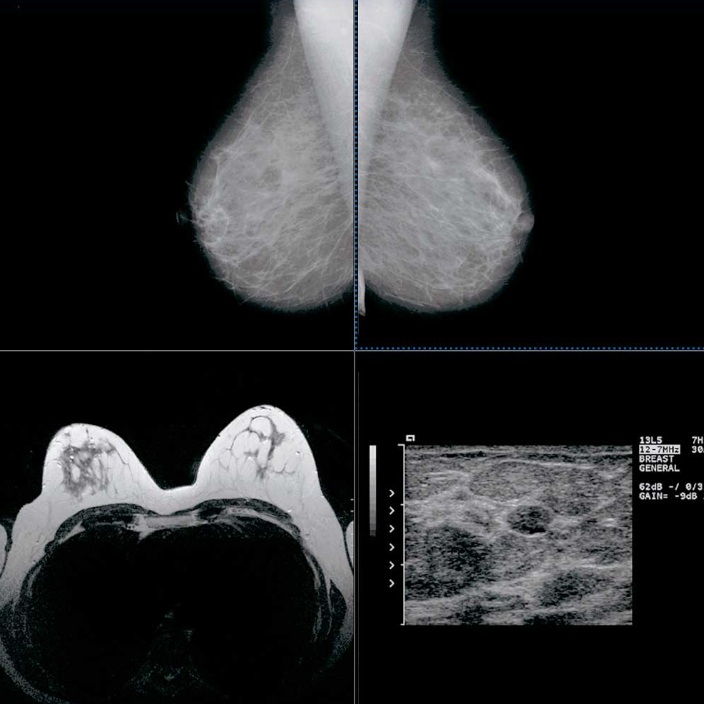

Ciudad de México – Febrero de 2026 – En un contexto donde la mortalidad por cáncer de mama en México ha alcanzado uno de sus niveles más altos en décadas —con una tasa de 19.8 defunciones por cada 100 mil mujeres—, ALIA Health y ÜMA Tech IA anunciaron el desarrollo conjunto de ALIA Health Risk Platform, una plataforma basada en inteligencia artificial orientada a la predicción y estratificación del riesgo de cáncer de mama a cinco años, a partir de mamografías de la práctica clínica habitual.

ALIA Health es una spin-off científico-tecnológica surgida de TecSalud, el sistema de salud del Tecnológico de Monterrey, una de las instituciones académicas y médicas más reconocidas de América Latina. La plataforma integra Mammorisk+, un modelo de inteligencia artificial desarrollado en el ecosistema clínico-académico del Tecnológico de Monterrey.

Mammorisk+ es un modelo predictivo, entrenado con datos reales de práctica clínica y diseñado para estimar la probabilidad futura de desarrollar cáncer de mama en un horizonte de cinco años, exclusivamente en mujeres con mamografías sin hallazgos sospechosos. Su objetivo es actuar antes del diagnóstico, en la etapa donde se definen estrategias de prevención, seguimiento y personalización del tamizaje.